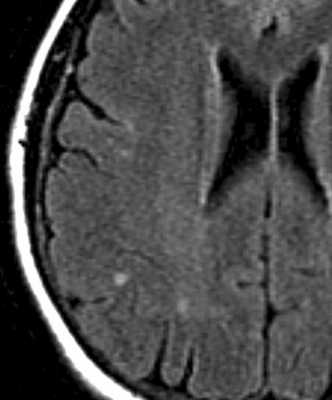

При МРТ головного мозга выявляется менингит и очаги в белом веществе. Менингит лучше виден при МРТ головного мозга с контрастирование, причем отмечается усиление не только оболочек, но и черепных нервов. Очаги в головном мозге неспецифические, светлые на Т2-взешенных МРТ. При МРТ головного мозга с контрастирование очаги могут усиливаться.

МРТ головного мозга. Т2-взвешенная аксиальная МРТ типа FLAIR. Болезнь Лайма.